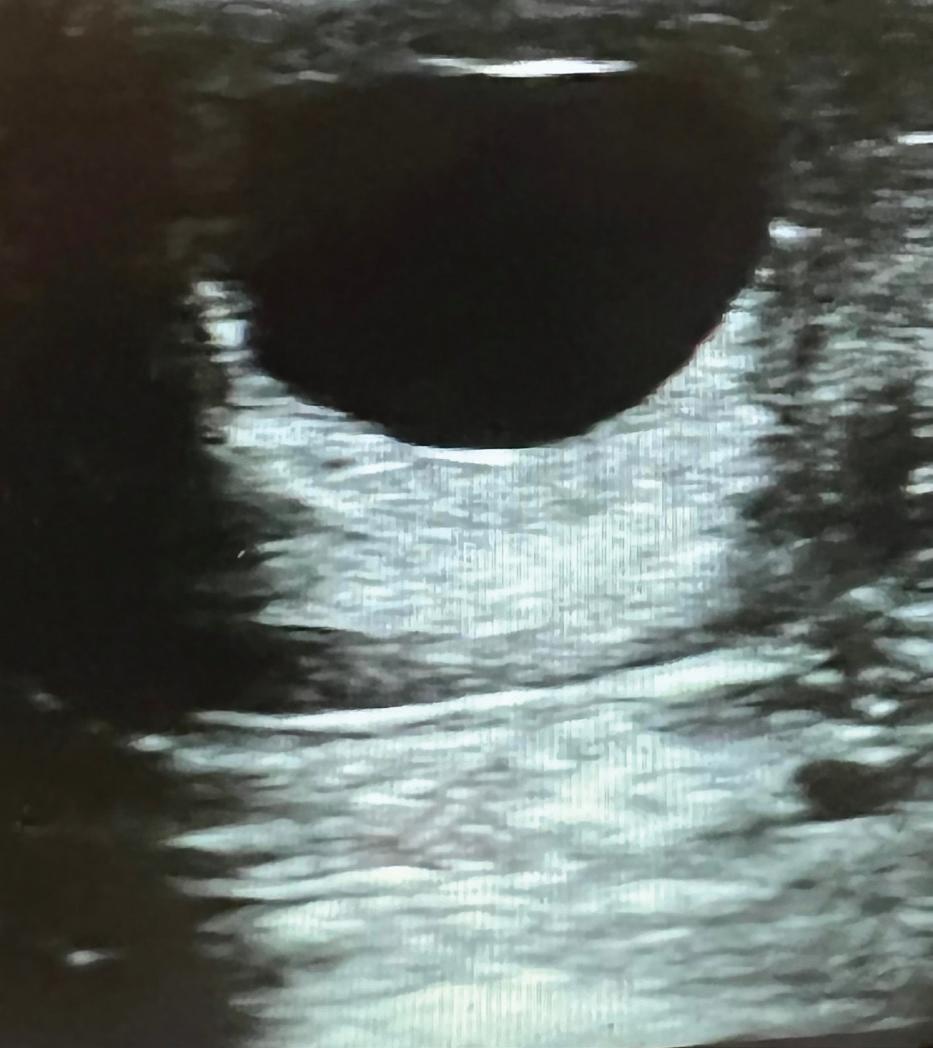

Du kan med fordel starte i marts/ april med at få din hoppe undersøgt. Her anbefaler jeg en skanning af hoppens livmoder og æggestokke. Der ser man, om der er normale forhold i livmoderen, at der eksempelvis ikke står væske eller mange cyster.

"På æggestokkene ser man efter follikler (æg) og gule legemer. Man kan også se, om hoppen er i cyklus, i overgang eller ikke er gået i gang med sine brunster for året endnu"

På æggestokkene ser man efter follikler (æg) og gule legemer. Man kan også se, om hoppen er i cyklus, i overgang eller ikke er gået i gang med sine brunster for året endnu.